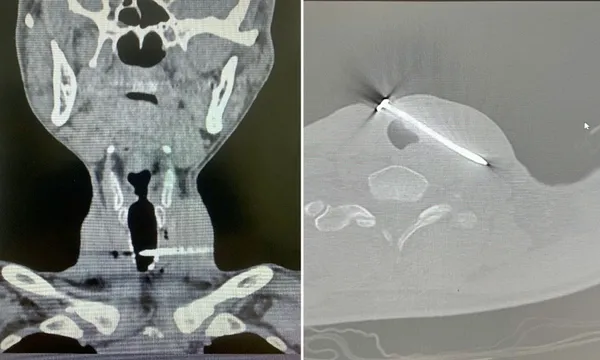

Tại Khoa Cấp cứu, bệnh nhân lập tức được xử trí theo quy trình khẩn cấp và chuyển chụp cắt lớp vi tính vùng cổ-ngực để đánh giá tổn thương.

Kết quả cho thấy, dị vật xuyên qua thành bên trái khí quản và đi qua đường đi của tĩnh mạch cảnh trong trái, một tổn thương cực kỳ nguy hiểm, có nguy cơ gây suy hô hấp cấp, sốc mất máu và tử vong nếu không được can thiệp kịp thời.